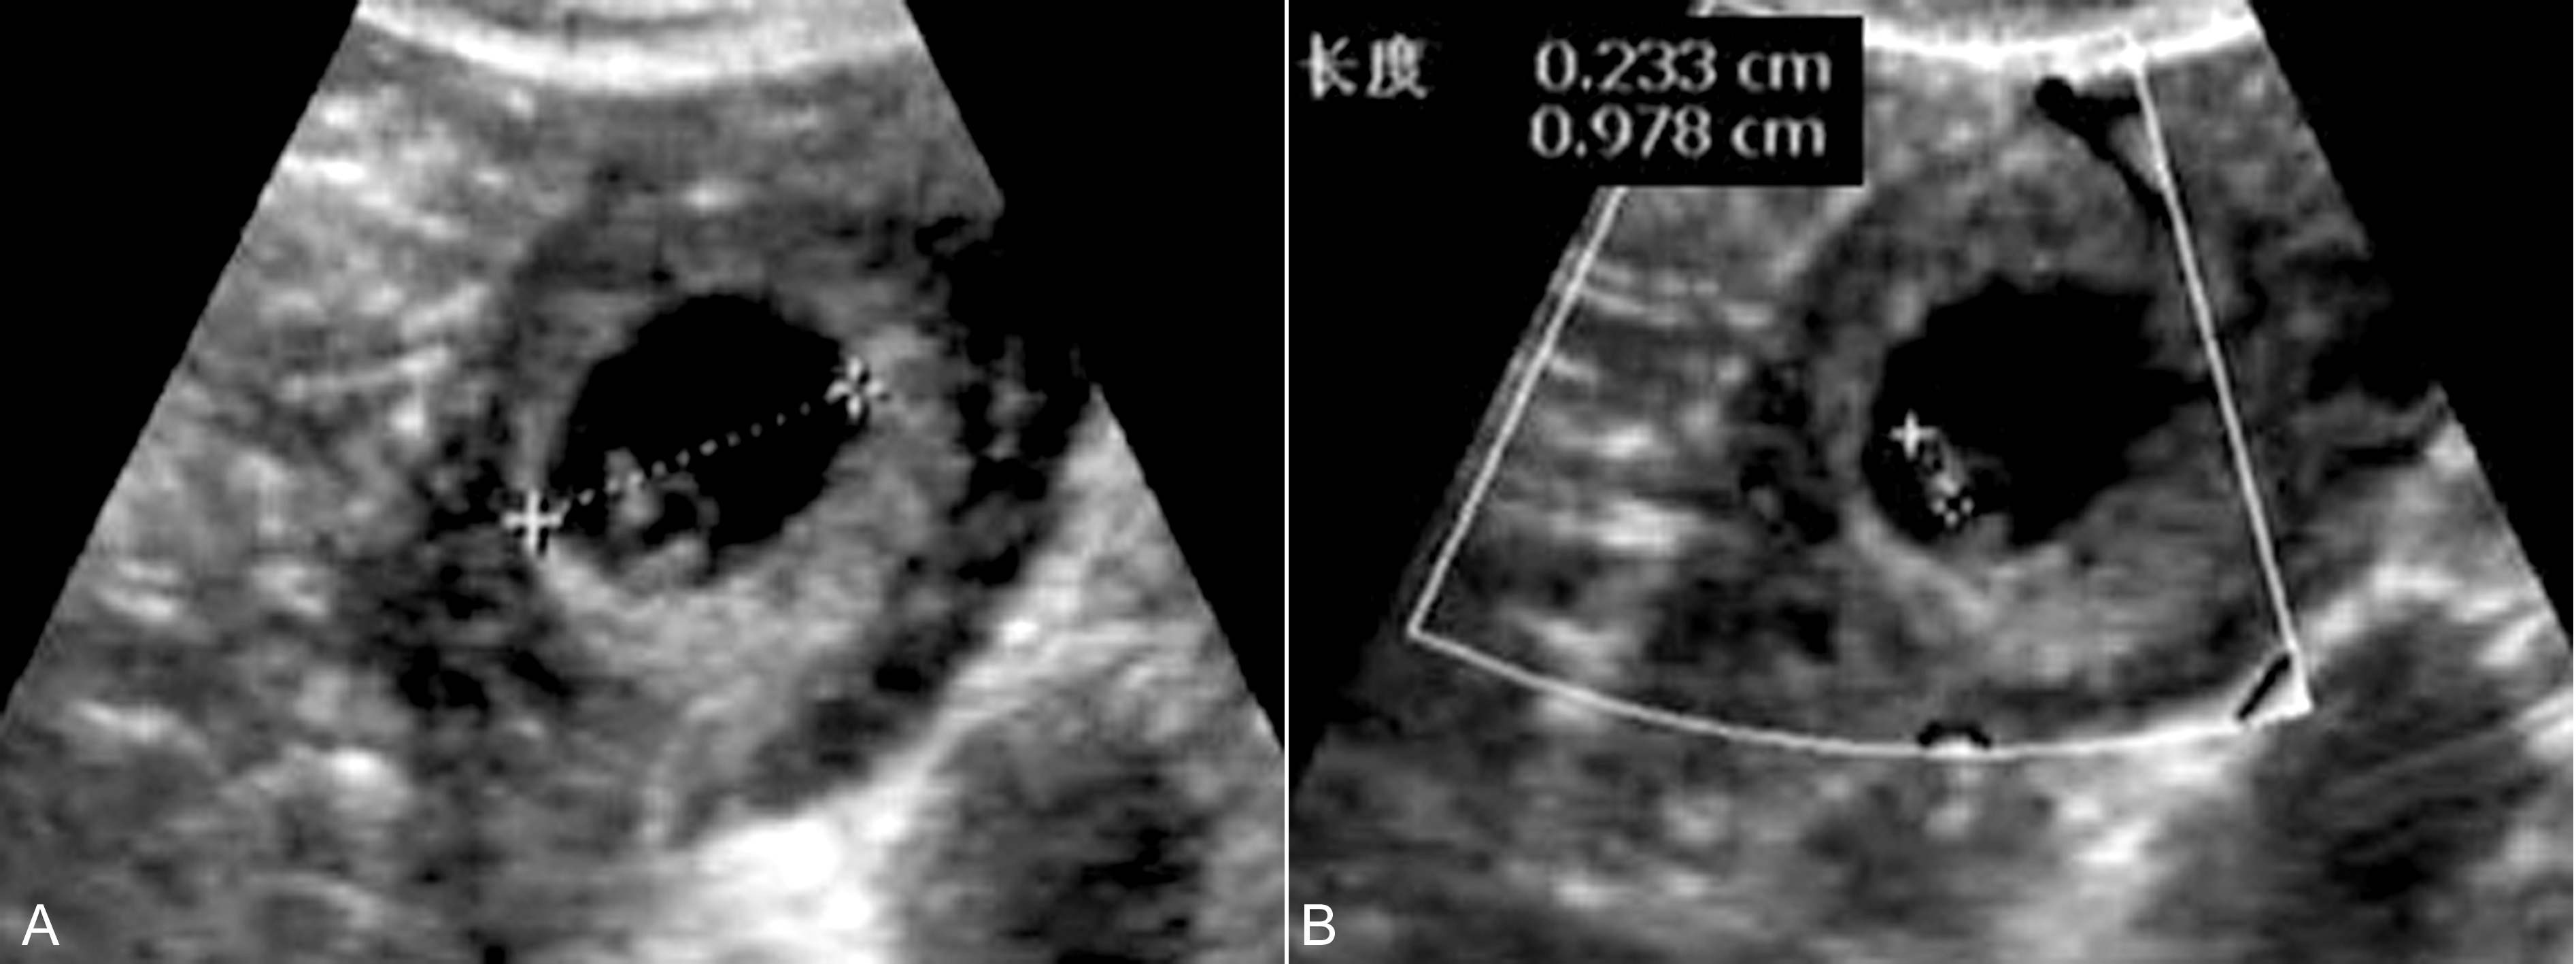

2、附件区团块 输卵管妊娠未破时显示为附件区圆形或椭圆形团块,形态规则,但内壁整齐、清晰(图3)。一般认为,单纯性囊性包块诊断输卵管妊娠的几率不足5%,显示为混合性包块时提示异位妊娠的可能性超过90%。团块内部呈混合性回声或显示典型的孕囊回声(图3,图4),部分(10%~20%)可以显示卵黄囊、胚胎回声或/和胎心搏动(图3,图4), 甚至可以显示胎动。破裂后常可见由妊娠组织、血凝块和周围组织或器官等形成的不规则团块,边缘不清晰、内部回声不均匀,多数区域显示为较低的回声(图5)。

图3 输卵管壶腹部妊娠:A:附件区示局限性回声;B:内部显示无回声及卵黄囊(YS)

图4 输卵管妊娠:右侧附件区显示完整孕囊回声,胚胎2.3mm